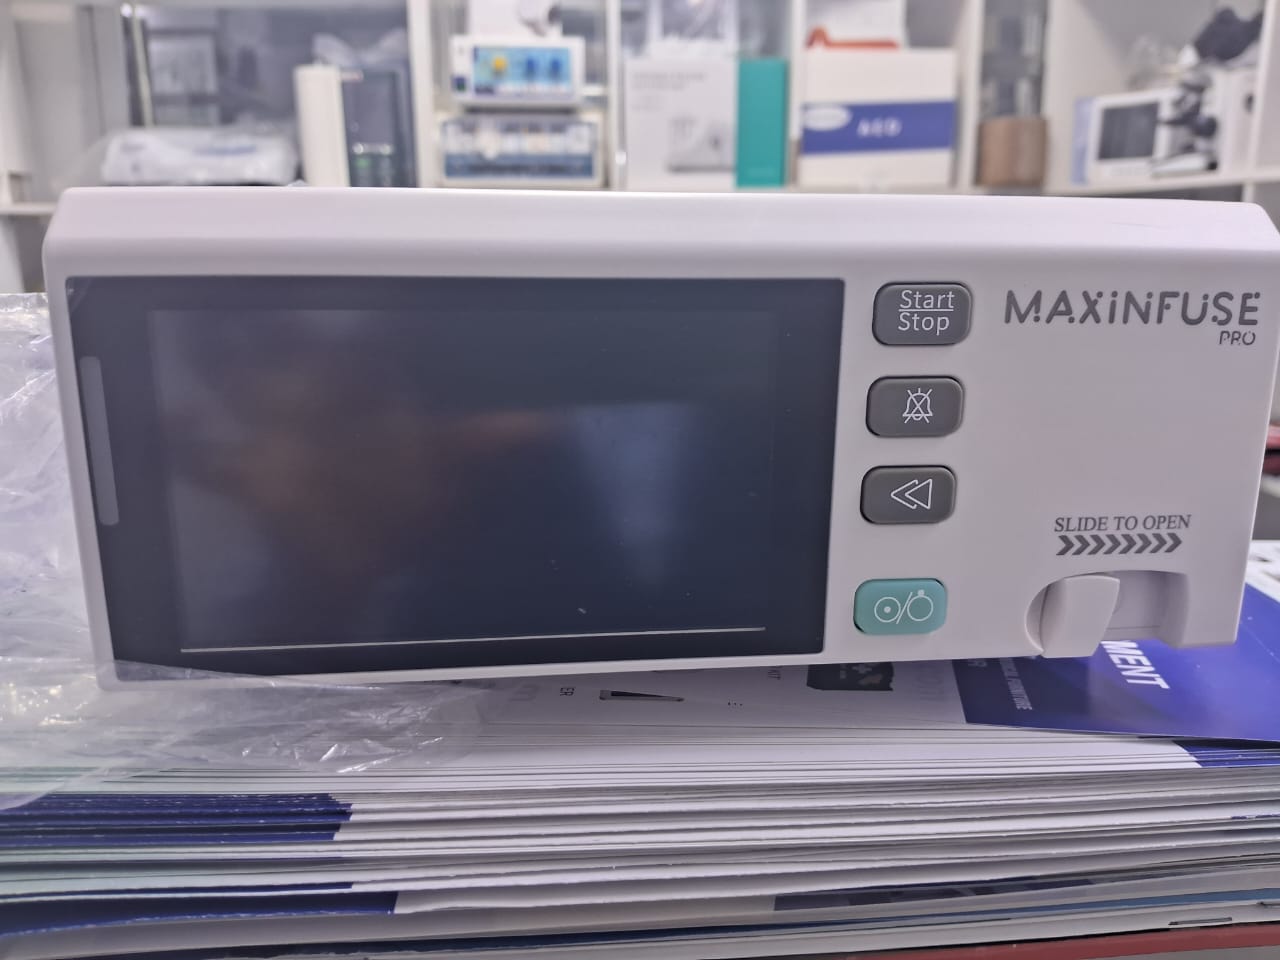

INFUSION PUMP - PULSEMEDUK

INFUSION PUMP - PULSEMEDUK